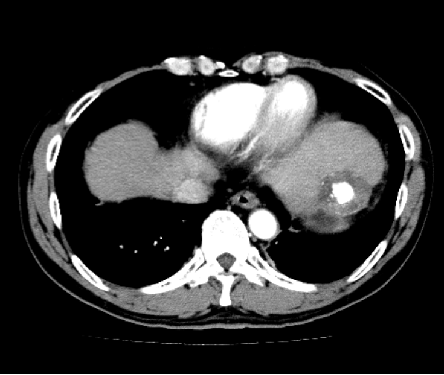

2015年5月(半年后)复查:

2016年2月复查:

S2新发病灶:13mm×16mm

2016年12月复查:

2016.05 直径约13mm

2016.12 6mm×13mm